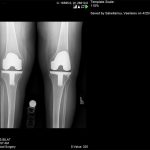

Ο ορθοπεδικός – χειρούργος Βασίλειος Σακελλαρίου στην Αθήνα αντιμετωπίζει επιτυχώς κάθε είδους κακώσεις γόνατος και ισχίου. Παρακάτω παρουσιάζονται πολλές περιπτώσεις κακώσεων που αντιμετωπίστηκαν επιτυχώς από τον χειρούργο – ορθοπεδικό. Δείτε τις αναλυτικά: